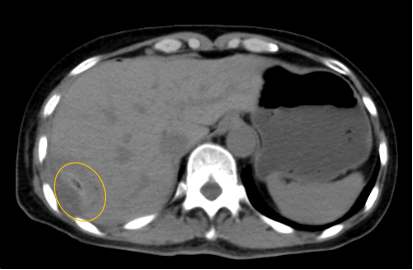

入院后,影像診療中心立即給李女士完善了CT和MR檢查,發(fā)現(xiàn)病變位于肝包膜下,臨近膈肌,消融治療過程中有并發(fā)損傷膈肌的可能,難度較大,但是采用精準(zhǔn)影像定位是可以完成的。陳寶瑩主任立即與腫瘤三病區(qū)劉金鵬主任聯(lián)系,并與影像微創(chuàng)治療小組進(jìn)行MDT討論:患者為卵巢癌肝右葉包膜下單發(fā)轉(zhuǎn)移瘤,最長徑不超過3cm,患者對局部治療的主觀愿望強(qiáng)烈,符合消融治療專家共識,遂制定了影像引導(dǎo)下局部消融治療聯(lián)合全身治療的綜合治療方案。

針對這個特殊部位的腫瘤,要想消融完全,那么膈肌損傷的風(fēng)險就很高,陳寶瑩主任帶領(lǐng)影像微創(chuàng)亞專業(yè)組成員仔細(xì)閱讀CT圖像,設(shè)計(jì)進(jìn)針路徑,結(jié)合MR圖像確定腫瘤活性范圍,制定了周密而詳盡的消融計(jì)劃。臘月二十九,即住院第二天影像微創(chuàng)治療小組圓滿為患者完成了腫瘤微波消融治療,觀察24小時后出院回家過年。術(shù)后48小時隨訪患者無明顯不適,術(shù)后7天隨訪,患者肝功、血常規(guī)等各項(xiàng)指標(biāo)均恢復(fù)正常。